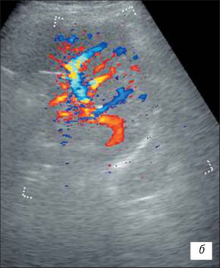

Ехограма гіпоплазії нирки

В-режимі(а),

В-режимі ЦДК (б, в).

Гемодинамічні показники артеріального кровотоку в нирковій артерії: Vps– 54 см/с, Ved– 22 см/с, RI– 0,4, PI– 0,7.

В-режимі (а)

В-режимі ЦДК (б).

На даному УЗД визначають зменшену в розмірах нирку з порушенням правильності її контурів, нирка насилу диференціюється від навколишніх тканин; різко порушена або відсутнє кортико-медуллярная диференціювання; візуалізуються дифузні нерівномірні зміни паренхіми нирки з гетерогенним підвищенням эхогенности; дилатація чашечно-мискової системи; виражене збіднення судинного малюнка ураженої нирки із зниженням швидкісних характеристик артеріального ренального кровотоку (10 – !!).